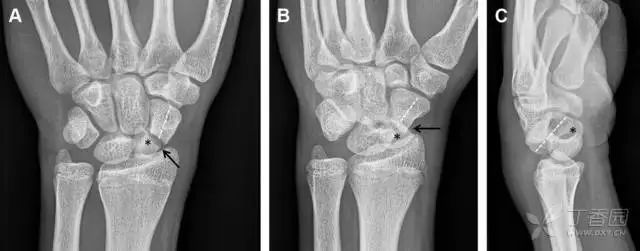

舟状骨骨折

舟状骨骨折 60%~70% 发生于腰部,15% 发生于近极, 10% 发生于远极, 8% 发生于远端关节面。除了常规的前后位、侧位、斜位片外,还需要拍专门的舟状骨位片(腕关节尺偏,以舟状骨为中心的腕关节前后位片),特别是鼻烟壶有压痛时。

图 2 舟状骨骨折 (A、B)第 1 例患者,舟状骨远极关节内骨折(白色箭头),斜位片显示较清楚(B);(C、D)第 2 例患者,舟状骨腰部骨折(虚线箭头),斜位片显示较清楚(D);(E~H)第 3 例患者,舟状骨近极骨折,常规 X 线片均未看到骨折,而在舟状骨位片上才能见到骨折(虚线圆)。